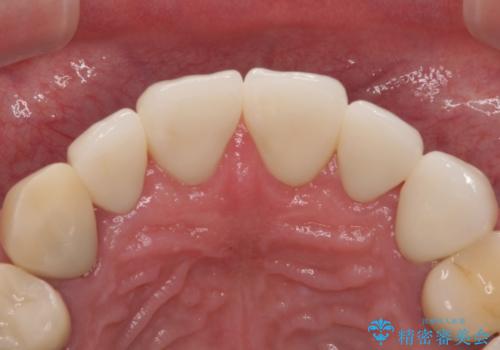

- 患者様は「前歯の見た目をきれいにしたい」というご希望で来院されました。

拝見すると、上顎前歯部にはCR充填(レジン修復)が繰り返し行われており、つぎはぎ状になっていました。そのため、

色調が不自然

形態にばらつきがある

笑ったときに治療跡が目立つ

といった審美的なお悩みが認められました。

また、右上側切歯は根管治療が必要な状態でした。

右上側切歯に対して根管治療を行い、その後右上側切歯から左上犬歯まで計5本をオールセラミッククラウンで補綴する治療計画をご提案しました。